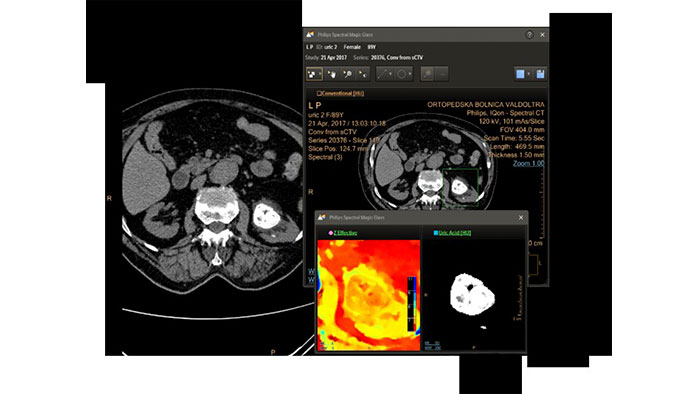

- Spectral Light Magic Glass

-

CT Spectral Light Magic Glass

Review spectral data in a range of not spectral-enhanced CT applications

Allows retrospective use of spectral data that was saved in a series of spectral base images (SBI).

The fast launch of LMG allows review and identification of the most relevant results to be launched into the application for further analysis.

Benefits

- The option is available from the following applications: Brain Perfusion, Functional CT, Liver Analysis, PAA, TAVI, Acute Multifunctional Review, Virtual Colonoscopy.

- Spectral Magic Glass can be launched only for CT images or images created on the Philips IQon Spectral CT.

- Spectral Magic Glass on PACS

-

CT Spectral Magic Glass on PACS*

IQon Spectral CT Functionality

IQon Spectral CT is the only scanner to offer CT Spectral Light Magic Glass and CT Spectral Magic Glass on PACS, helping radiologists review and analyze multiple layers of spectral data at once, including on their PACS.

Benefits

- On-demand simultaneous analysis of multiple spectral results for an Region Of Interest (ROI).

- Integrates into a health system’s current PACS setup for certain PACS vendors.

- Spectral results viewable, during a routine reading.

- Enterprise-wide spectral viewing and analysis allows access to capabilities virtually anywhere in the organization.

* Standard with the CT Spectral option on IntelliSpace Portal.